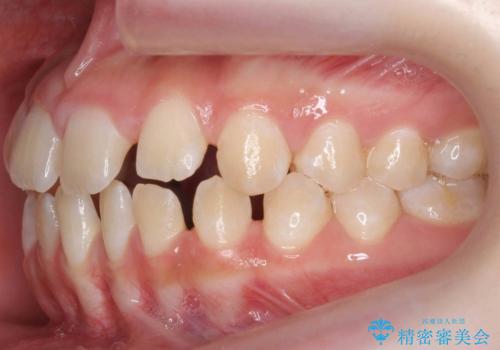

- 前歯の隙間を主訴に来院。

顎の大きさに比べて歯が小さく、隙間が目立っていました。

マウスピース矯正で隙間を閉じる処置を行いました。

隙間を閉じる際、奥歯が倒れたため、途中ワイヤー矯正を併用しています。

上の前歯の隙間を閉じながら前歯を後方に下げているため、口元もひっこみ、口が閉じやすくなりました。